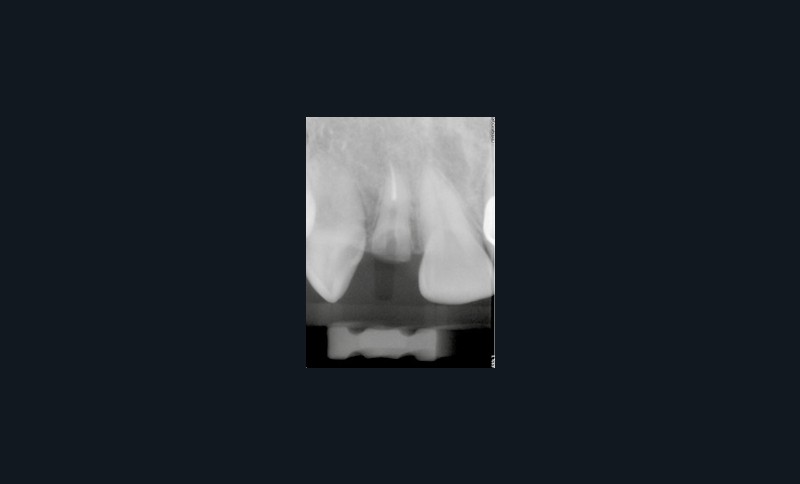

Le développement croissant des systèmes d’imagerie 3D à faisceau conique (CBCT : Cone Beam Computed Tomography), couplé à une démocratisation des logiciels de navigation et de planification implantaire, jusqu’à récemment onéreux, a permis une systématisation et une généralisation de leur utilisation à toutes les situations cliniques, rendant notre geste clinique plus prédictible.

Nous allons décrire, étape par étape, les différents temps cliniques permettant l’élaboration d’un guide chirurgical et la place de la CFAO de la planification à la réalisation du temps chirurgical au travers d’un cas clinique (fig. 1).